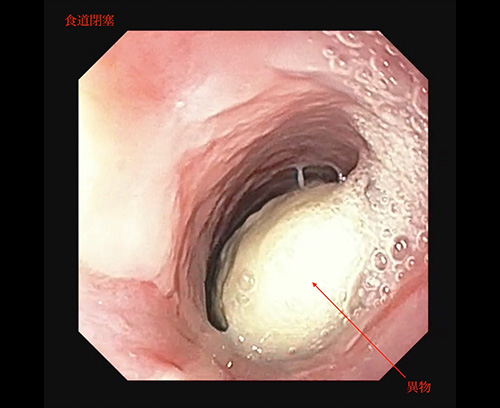

食道異物